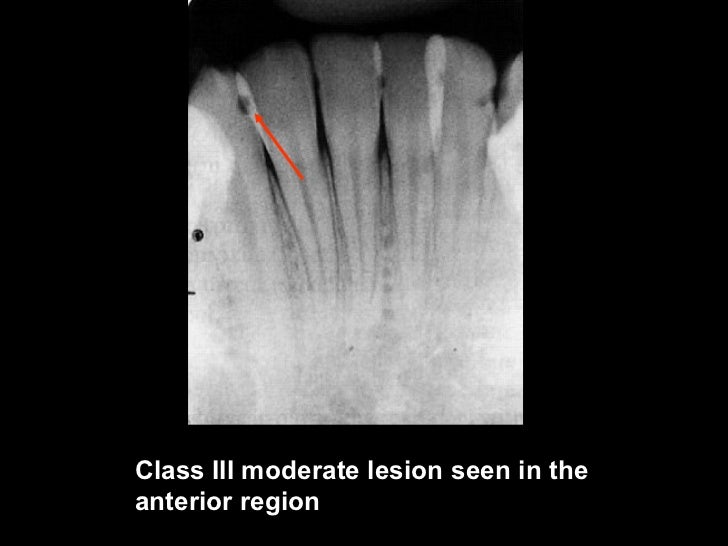

Figure 1 from Management of high caries risk and high caries activity